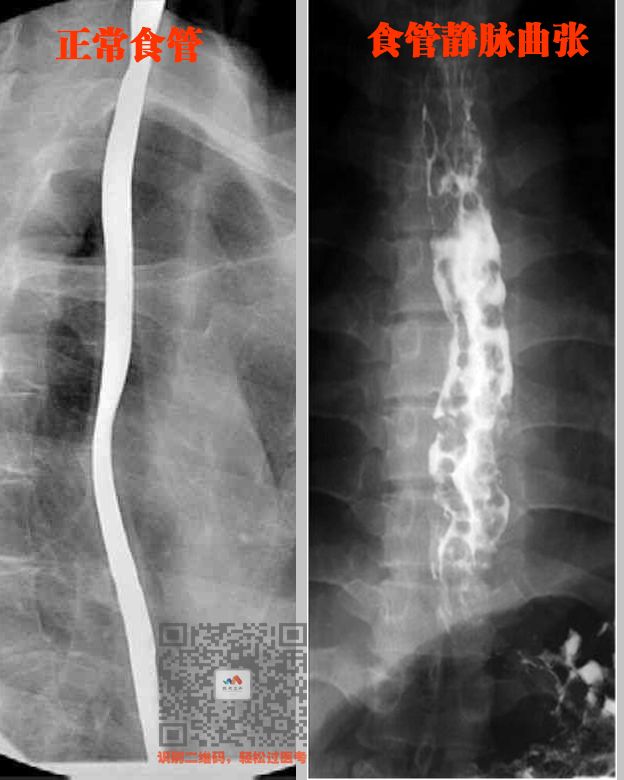

① 食管静脉曲张

特点:串珠状、蚯蚓状的充盈缺损

就是食管粘膜下的静脉增粗、弯曲

然后再胃镜下面,凹凸不平

看着跟大腿静脉曲张一样

看图

这些凸起的地方,钡剂就没法填充

所以就会显示黑色,钡剂填充地方显示白色

所以,就成了这样啦

(串珠样充盈缺损)